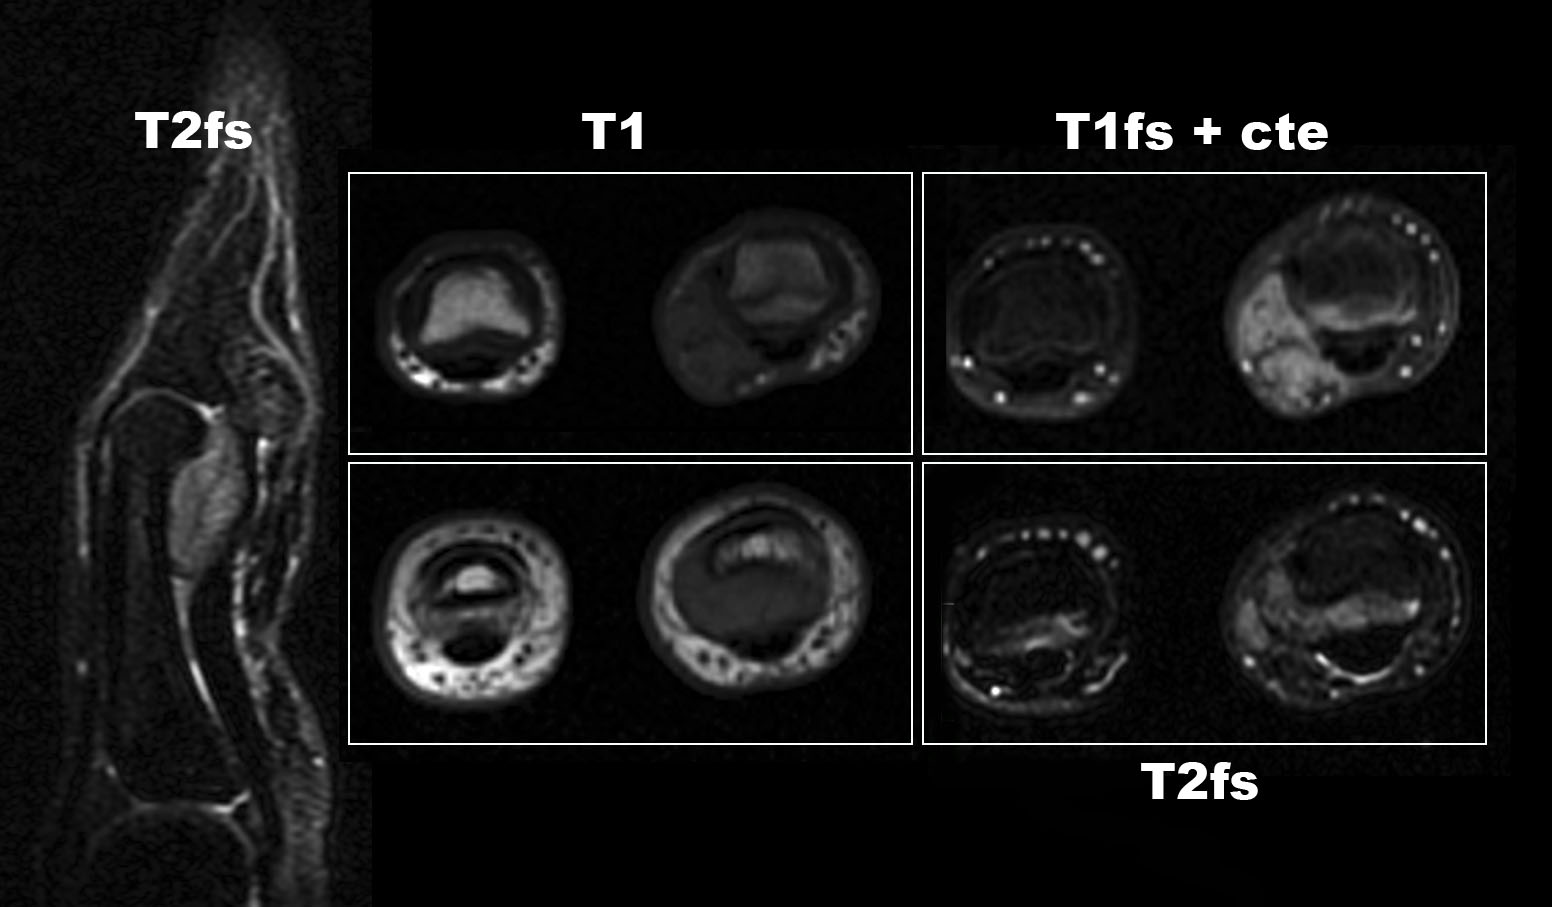

Se solicitan pruebas de imagen: RX, ECO, RM.

2. ¿Como describirías los hallazgos en RM?

- A. Lesión dependiente de la polea A2.

- B. Tumoración de partes blandas relacionada con la vaina tendinosa.

- C. Sinovitis dependiente del espacio interfalángico.

- D. Tumoración dependiente de la falange media con componente de partes blandas.

- E. Tumoración de aspecto vascular.

3. Ante los hallazgos en imagen, ¿cuál es tu diagnóstico?

- A. Artritis con panus.

- B. Sinovitis con nódulo condromatoso.

- C. Tumor de células gigantes tenosinovial.

- 4. Fibromatosis.

- E. Hematoma.